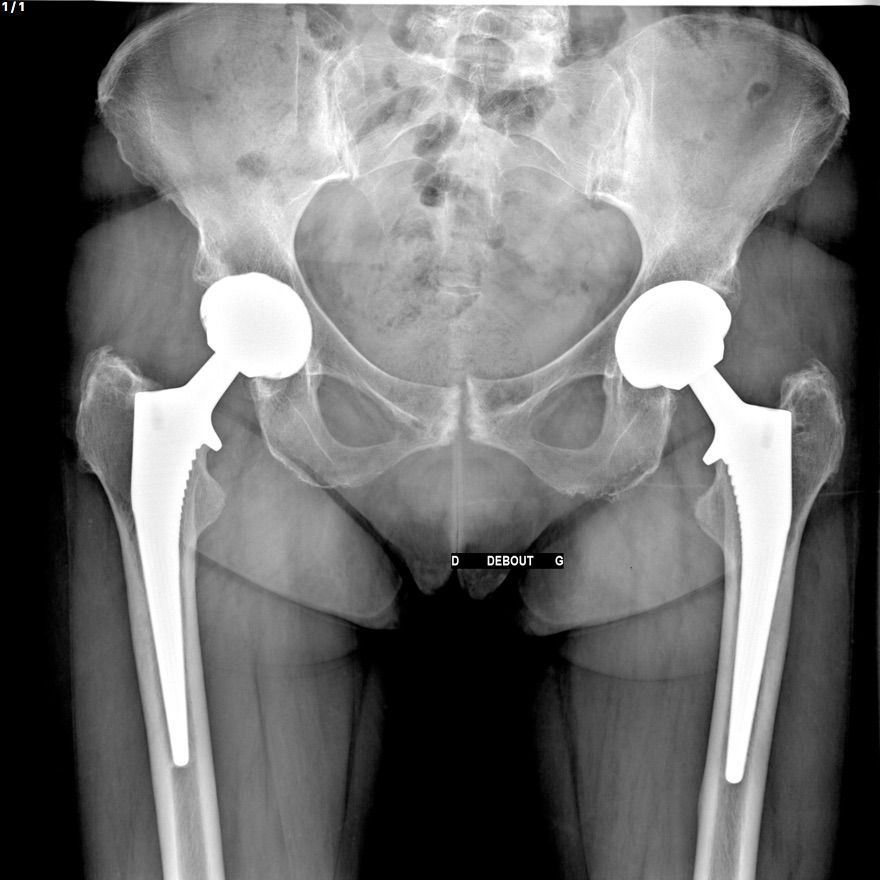

La prothèse se descelle (bouge par rapport à l'os) à cause de l'usure, d'une infection chronique ou de luxations répétées.

L'opération

Remplacement de la ou des pièces défaillantes. Si l'os est très abîmé, une greffe osseuse peut être nécessaire. En cas d'infection : délai de 6 semaines entre l'ablation et la réimplantation possible. Durée : 2 à 3 heures. Hospitalisation : 3 à 5 jours.

Infection (5 à 10 %), hématome, phlébite, luxation, fracture, inégalité de longueur des jambes.

Résultats attendus

Bonne récupération dans la majorité des cas. Durée de vie : 15 ans.